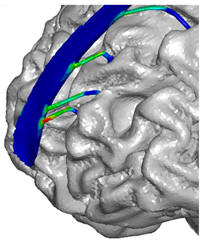

| Frontal veins | ![]() | ![]() | ![]() |

| Parietal veins | ![]() | ![]() | |

| Occipital veins | ![]() | ![]() |